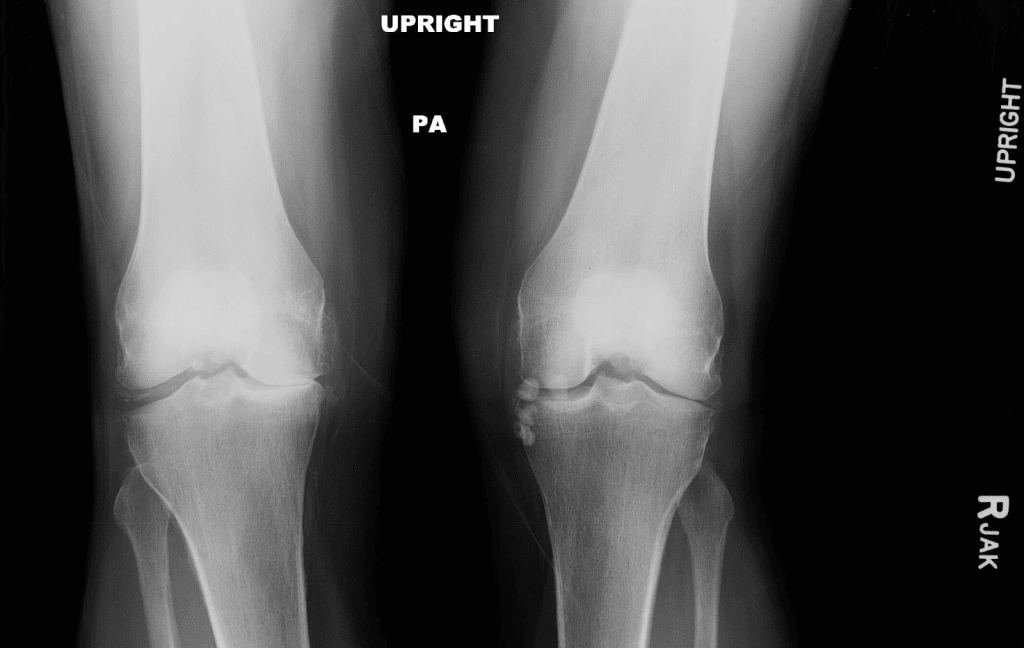

X-Ray Imaging for Osteoarthritis Detection

X-ray imaging is key in spotting osteoarthritis by showing joint damage. It’s a top choice because it clearly shows bone and joint spaces.

How X-Rays Visualize Joint Damage

X-rays are great at showing joint damage from osteoarthritis. They capture images of bones and the spaces between them. This lets doctors see how much damage there is. Joint space narrowing and bone spurs are signs of osteoarthritis seen on X-rays.

Joint Space Narrowing on X-Rays

One key sign of osteoarthritis is joint space narrowing. This can be seen on X-rays. When cartilage wears down, the space between bones gets smaller. X-rays help doctors measure how much narrowing there is, helping with diagnosis and treatment.

Bone Spurs and Osteophyte Detection

Bone spurs, or osteophytes, are abnormal bone growths from osteoarthritis. X-rays can spot these growths, showing how much damage there is. The size and number of bone spurs tell doctors about the osteoarthritis’s stage and severity.

| Osteoarthritis Feature | X-Ray Finding | Clinical Significance |

| Joint Space Narrowing | Reduced space between bones | Indicates cartilage loss and osteoarthritis progression |

| Bone Spurs/Osteophytes | Abnormal bone growths | Signifies joint damage and osteoarthritis severity |

| Sclerosis | Increased bone density | Reflects chronic osteoarthritis and bone remodeling |

Common X-Ray Findings in Different Joints

X-rays show different things in different joints with osteoarthritis. For example, knee osteoarthritis often shows joint space narrowing, osteophyte formation, and subchondral sclerosis. Hand osteoarthritis might show joint space narrowing, osteophytes, and bony erosions.

Knee Osteoarthritis Imaging

X-rays are often used to check knee osteoarthritis. They show joint space narrowing and bone spurs. MRI is also valuable for assessing soft tissue damage and cartilage loss.